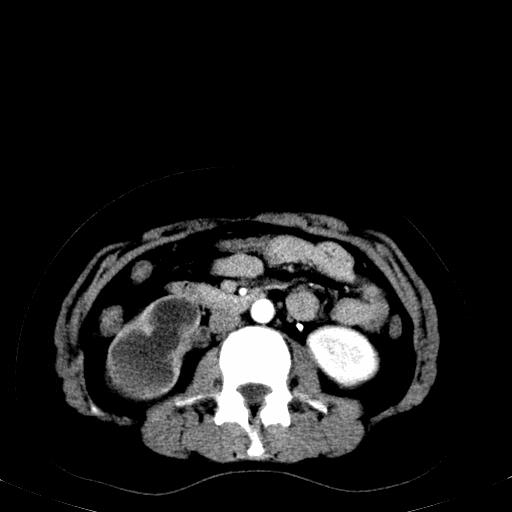

患者体检发现右肾体积增大,怀疑右肾积水

右肾重度积水,以肾盏积水明显,有分隔,上段输尿管轻度扩张,管壁增厚,考虑肾结核可能,请结合尿检查,胸部拍片排除肺结核。

右肾重度积水,建议ct向下扫描或逆行造影,左肾及左输尿管结石 .

患者尿常规正常,b超未发现明显结石,自身也无明显感觉异常。

请问多囊肾与肾积水怎么鉴别